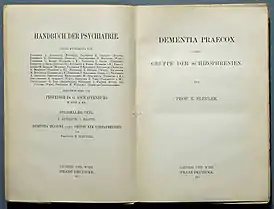

En realidad, la historia de la esquizofrenia como entidad nosológica es muy reciente. En 1853, el psiquiatra francés Bénédict Morel acuñó el término: demence précoce, en francés «demencia precoz», para describir un trastorno mental que afectaba a adolescentes y adultos jóvenes y que con el tiempo evolucionaba a un deterioro del funcionamiento mental, y a la incapacidad del sujeto (ese deterioro es a lo que se refiere la palabra 'demencia'),[29] en contraposición con la demencia clásica, asociada a la senilidad. Posteriormente, en 1886, con el alienista alemán Heinrich Schule, y más tarde, por Arnold Pick en 1891, se utilizó el término: dementia praecox en un informe sobre un caso de trastorno psicótico. En 1871 Ewald Hecker definió al mismo síndrome de demencia juvenil como hebefrenia, destacando su rápida evolución hacia la «estupidez, embrutecimiento y desorganización de las funciones psíquicas».[30] Tres años más tarde Karl Kahlbaum observó otra forma de alienación mental caracterizada por trastornos motores, sensoriales y mutismo que denominó catatonia.[31]

El enfoque contemporáneo del concepto de esquizofrenia se inició en 1887 con Emil Kraepelin, que estableció una amplia separación en la clasificación de los trastornos mentales entre la dementia praecox y los trastornos de estado de ánimo (llamados maniaco-depresivos, que incluían tanto la depresión unipolar como la bipolar), originada en un proceso sistémico quiescente, y llegó también a la conclusión en 1898 de que la hebefrenia y la catatonia eran subtipos de una sola enfermedad.[32][33][34] Después de abundantes observaciones de sus pacientes, consiguió sistematizar una buena cantidad de entidades psicopatológicas que estaban confusas hasta entonces y distinguió una forma de «demencia» que aparecía en los jóvenes, separándola de otras formas de enfermedad mental, como la psicosis maníaco depresiva, incluyendo tanto la depresión unipolar como la bipolar. Describió el curso a lo defectual y el temprano inicio de esta forma de dementia praecox. Le dio mayor importancia a los síntomas «negativos» como «debilitamiento de la voluntad» y la falta de un «desarrollo personal».[35]

Años más tarde se puso de manifiesto que el trastorno descrito como «demencia precoz» no conduce necesariamente a un deterioro mental, ni solo afecta a personas jóvenes,[30] y en 1908 el psicólogo suizo Eugen Bleuler sugirió que el nombre era inadecuado, porque el trastorno no era una «demencia», es decir, no llevaba necesariamente a un deterioro de funciones mentales como en la demencia senil tipo enfermedad de Alzheimer; muchos pacientes sí mejoraban y además, ocasionalmente se iniciaba en personas maduras.[39] Bleuler sugirió la palabra «esquizofrenia» para referirse a una escisión de los procesos psíquicos consistente en la pérdida de correspondencia entre el proceso de formación de ideas y la expresión de emociones y para diferenciarlo de la enfermedad maníaco-depresiva, en donde la expresión de las emociones de los pacientes refleja con precisión sus pensamientos mórbidos.[32] Hizo hincapié en que el trastorno fundamental era el deterioro cognoscitivo y lo conceptualizó como una división o «escisión» en la capacidad mental y propuso entonces el nombre con el que se conoce el trastorno hasta hoy.[31][40]